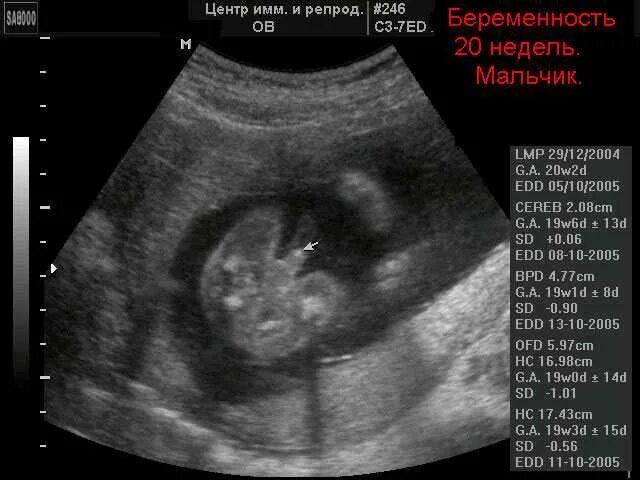

Узи определение пола ошибки